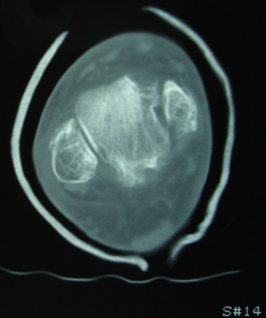

Продолжая тему представляю данные КТ нашей пациентки.

Вложение не в текстовом формате было извлечено…

Имя     : Скан 13.JPG

Тип     : image/jpeg

Размер  : 44517 байтов

Url     : http://weborto.net:8080/pipermail/ortho/attachments/20091107/a87a6ebe/attachment-0007.jpeg